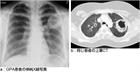

1. 多発血管炎性肉芽腫症(granulomatosis with polyangiitisGPA患者ではANCA(anti-neutrophil cytoplasmic antibodies)の陽性率は高い。腎症を伴う全身型の場合は80~90%で陽性である。また、頭頚部または肺のみに病変を認める限局型の場合は約60%で陽性である。したがって、GPAを疑う患者でのPR3-ANCA(c-ANCA)、MPO-ANCA(p-ANCA)測定は推奨される(推奨度1)